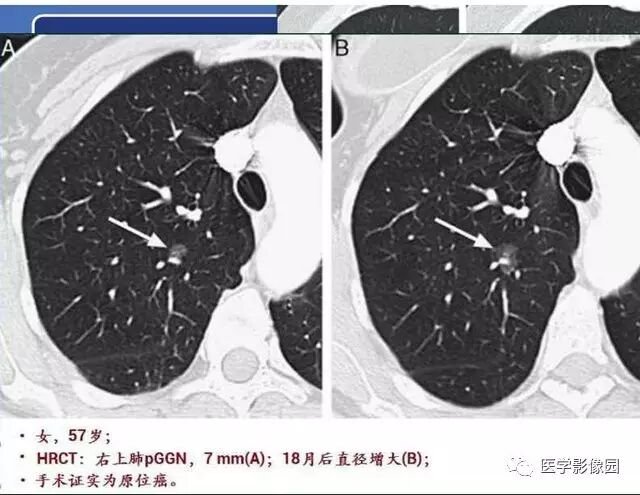

肺磨玻璃结节的CT诊断与临床处理策略